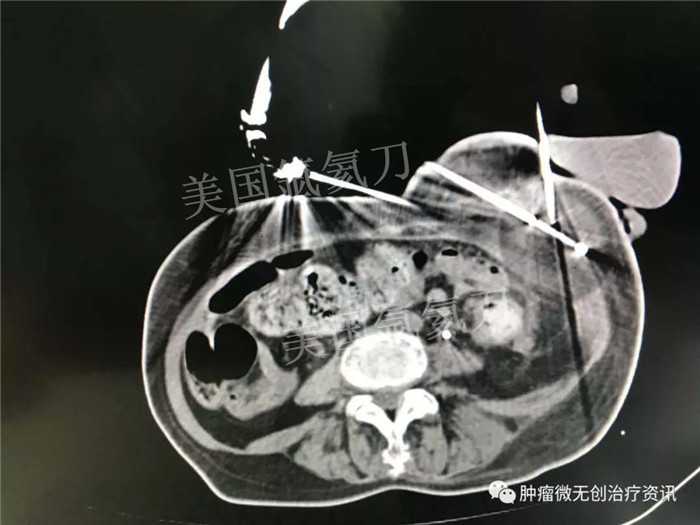

中美国际肿瘤医院氩氦刀冷冻消融治疗子宫颈癌左髂骨内侧转移病灶

患者女性,63岁,宫颈癌术后1年余。左髂骨内侧转移放、化疗后,患者左下肢疼痛持续无改善,今为求进一步治疗,就诊于中美国际肿瘤医院。结合患者情况,行氩氦刀冷冻消融治疗。此次治疗主要以止痛为主。